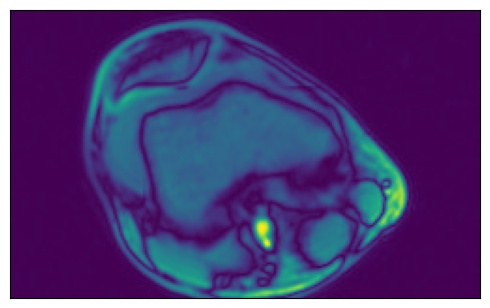

We can check that the data is equivalent in both representations:

ser00001_2d = [np.load(data_dir_2d / "SER00001" / f"{i}.npy") for i in range(4)]

plot_tensors(ser00001_2d[0], ser00001_2d[1], ser00001_2d[2], ser00001_2d[3])

../../../../_images/examples_general_data_loading_numpy_reader_dynamic_mode_6_0.png